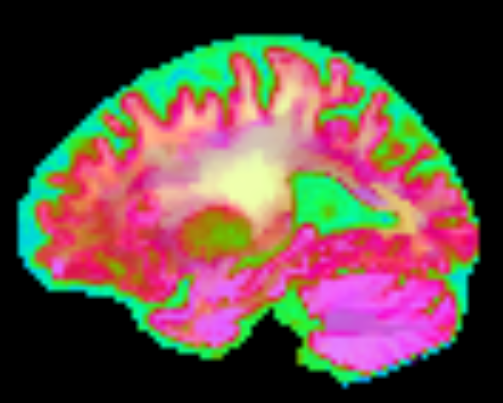

This project aims to develop a data-driven framework for analyzing diffusion MRI (dMRI) signals in healthy and tumor-affected brain tissue using dimensionality reduction techniques such as t-SNE, UMAP, and autoencoders. By embedding the complex, multi-dimensional dMRI signal into a low-dimensional space (e.g., 2–3 components per voxel), the goal is to generate interpretable maps that capture intrinsic microstructural features of brain tissue without relying on traditional biophysical models. These component maps will be quantitatively compared with established dMRI metrics to assess how well data-driven representations reflect known microstructural properties.

The study will further test whether low-dimensional representations derived from simpler acquisitions (e.g., single-shell) can approximate metrics that typically require advanced multi-shell data. Finally, the approach will be applied to individual tumor cases to explore how different components reflect tissue heterogeneity—distinguishing tumor core, edema, and infiltrated regions. The outcome will be a validated framework offering new ways to visualize, interpret, and simplify diffusion MRI data in both research and clinical contexts.